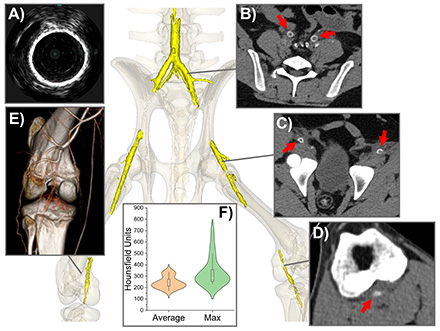

Peripheral Artery Calcification Disrupts Lower Extremity Biomechanics In a Swine Model

Abstract Body: Limb flexion imposes severe deformations on lower extremity arteries, altering blood flow and contributing to the progression of Peripheral Artery Disease (PAD) and treatment failure. While arterial calcification is associated with poor clinical outcomes and an elevated risk of amputation, its biomechanical effects remain poorly understood. Using a swine model of advanced arterial calcification, we investigated the impact of arterial calcium on limb flexion-induced biomechanics while controlling for confounding variables. Calcification was induced by delivering CaCl2 into the media and periadventitial spaces of the iliac, femoral, and popliteal arteries via a micro-needle catheter. This approach produced robust calcific lesions (Figure 1), clearly visible on computed tomography and intravascular ultrasound within 30 days, and closely mimicking human calcification in morphology, mechanics, and histology. Experimental (n=6) and control (n=27) animals were imaged with their limbs in straight and flexed positions (Figure 2). Reconstructed 3D arterial geometries revealed significant differences in diameters, foreshortening, tortuosity, and angulation between calcified and non-calcified arteries. Calcified arteries exhibited 15% larger diameters (7.1 vs. 6.2 mm, p=0.048) and accommodated 41% less foreshortening during flexion (1.29 vs. 1.49, p<0.01), resulting in increased tortuosity and sharper bends. Tortuosity increased by 61% in the external iliac artery (0.06 vs. 0.04), 49% in the superficial femoral artery (SFA, 0.20 vs 0.13), and 19% in the popliteal artery (PA, 0.36 vs. 0.30) (all p<0.01). Bending severity, assessed via inscribed sphere measurements and angles, was 52% greater at the inguinal ligament (11.4 vs 23.8 mm), 43% greater in the SFA (16.9 vs 29.7 mm), and 59% greater in the PA (5.9 vs 14.1 mm) (all p<0.01) in animals with calcific lesions. This porcine model replicates critical features of calcific human PAD in a rigorously controlled environment, enabling detailed biomechanical analysis. Furthermore, it provides a robust platform to evaluate the impacts and mechanisms of calcium-modifying treatments, offering valuable insights for improving therapeutic strategies. Our findings demonstrate that arterial calcification significantly impairs the ability of arteries to accommodate limb flexion, exacerbates bending and tortuosity, and likely contributes to impaired blood flow, PAD progression, and treatment failure.